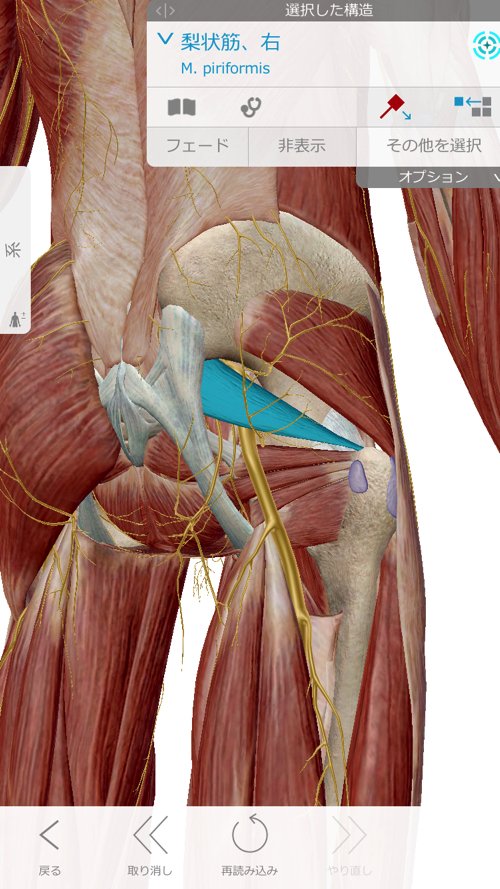

お尻付近も痛みが出ていて

最後に臀部付近の筋肉を緩めて調え直し腰の腱を調整して施術は終了です。